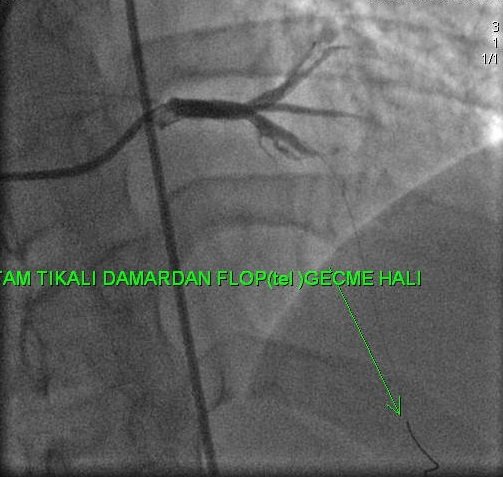

Başka merkezde CTO işlemine alınıp başarısız olup kliniğimize başvuran hastaya RCA uzun ve tandem CTO lezyonları özel mikro kateter ve teller ile geçilerek balon ve stent işlemleri başarıyla sonuçlandı.